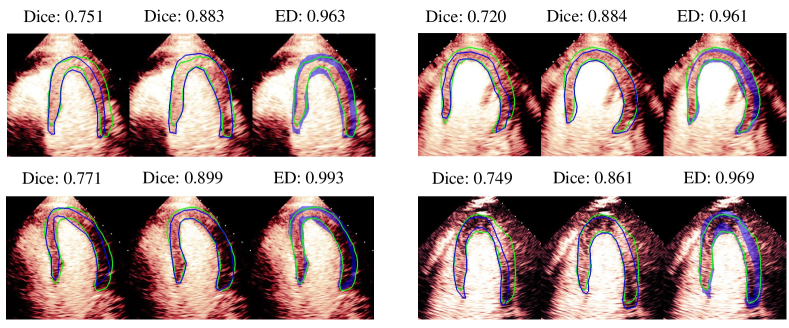

In Fig. 6, we show the evaluation comparison of four images using Dice and extended Dice. Images in each group represent the Dice evaluated by cardiologist 2, Dice evaluated by cardiologist 5 and extended Dice. It can be seen that there exist large variations in Dice when using different cardiologists’ annotations as the ground truth, which may lead to misjudgment during evaluation. For example, we may think the segmentation quality is low (Dice0.77) based on the annotation from one of the cardiologists, but the quality is actually pretty good based on the annotation from another one (Dice0.86). However, using extended Dice will alleviate the problem because all these images are considered good (extended Dice0.96).